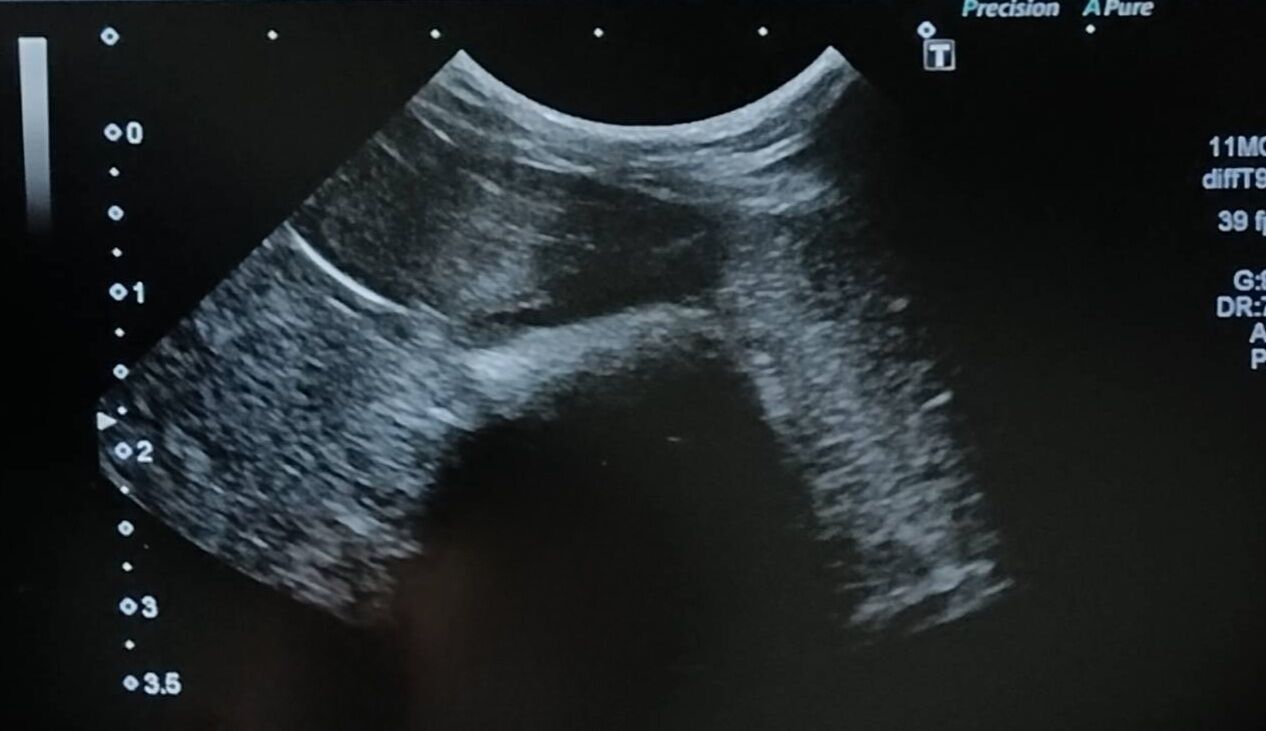

ひかるんくん【師走っこ】

牧草はアルファルファしか食べず、飲水量も極端に少ないため、膀胱に砂がたまりやすい体質です。

様子を見てエコー検査を行い、状況によりお薬で対処しています。

1/24 1880g エコー検査 お薬処方

前回は2024/10/30に通院でした。

最近は尿砂が出ていませんでしたが、エコー検査をしたところ、前回より膀胱の尿砂が増えていました。

お薬を継続し、経過観察となりました。